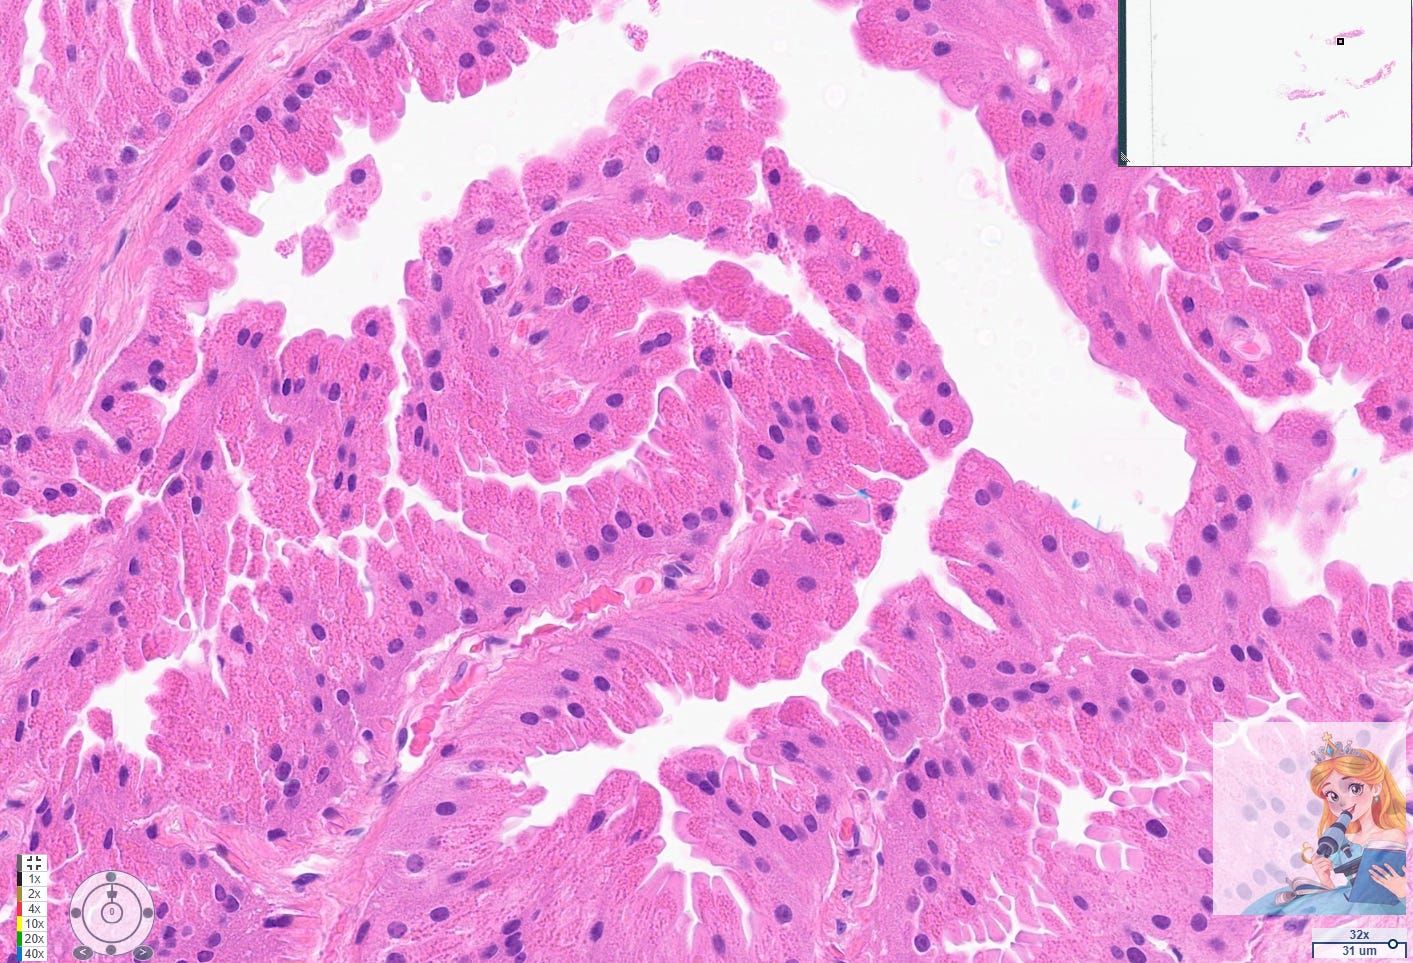

Apocrine cysts are a common manifestation of fibrocystic change in the breast, particularly in women over 25 years old. These cysts are lined by apocrine cells, which are characterized by abundant eosinophilic granular cytoplasm, round nuclei with pale chromatin, and prominent nucleoli. The apocrine lining may be cuboidal or columnar, and the cells typically have a low nuclear-to-cytoplasmic ratio and prominent apical snouts, reflecting apocrine secretion.[1-2]

Immunohistochemically, apocrine cells in these cysts consistently overexpress androgen receptor and lack estrogen and progesterone receptor expression, which can aid in their identification and distinction from other breast epithelial cells. It is rare that these stains need to be performed in daily practice. While some studies have explored the potential for apocrine metaplasia to be a precursor to malignancy, the overwhelming consensus is that cysts lined by apocrine cells with abundant eosinophilic cytoplasm and round nuclei are a benign and extremely common finding in women over 25 years old.[5][4]

Eosinophilic Cytoplasm + Bland Nuclei = Apocrine Change! This is your most reliable morphological indicator.